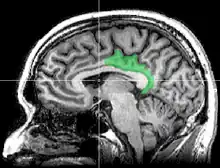

Cortex cingulaire postérieur

Le cortex cingulaire postérieur (CCP) est, dans le cerveau, une zone à l'arrière du cortex cingulaire ressemblant à une ceinture entourant le corps calleux.

- cortex cingulaire postérieur CCP, avec le même nom mais limité aux aires 23 et 31

Pour éviter les confusions, Brent A. Vogt appelle l'ensemble formé par le cortex cingulaire postérieur (CCP) et le cortex rétrosplénial (CRS), le gyrus cingulaire postérieur.